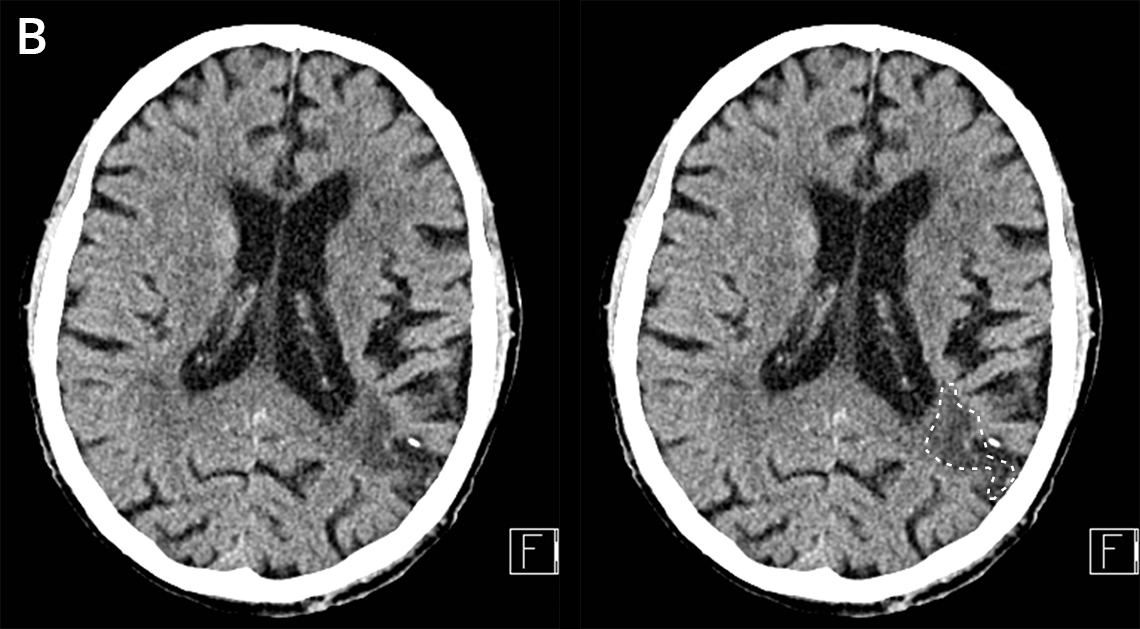

Aivoinfarkti pään TT-kuvassa MCA:n suonitusalueella.

Iäkäs mies kaatui ja löi päänsä. Potilaalla oli ennestään vanhan aivoinfarktin pohjalta oikean puolen heikkoutta. Kaatumisen jälkeen tajunnan taso oli lievästi laskenut ja oikea puoli oli tavallistakin voimattomampi.

B. Vasemmalla parieto-okkipitaalisesti on nähtävissä vanha infarktiharventuma (valkoinen katkoviiva). Vuotoja tai likvorkierron häiriöitä ei ole nähtävissä.

Kuvat: HUS Kuvantaminen, teksti: Tiina Lehtimäki